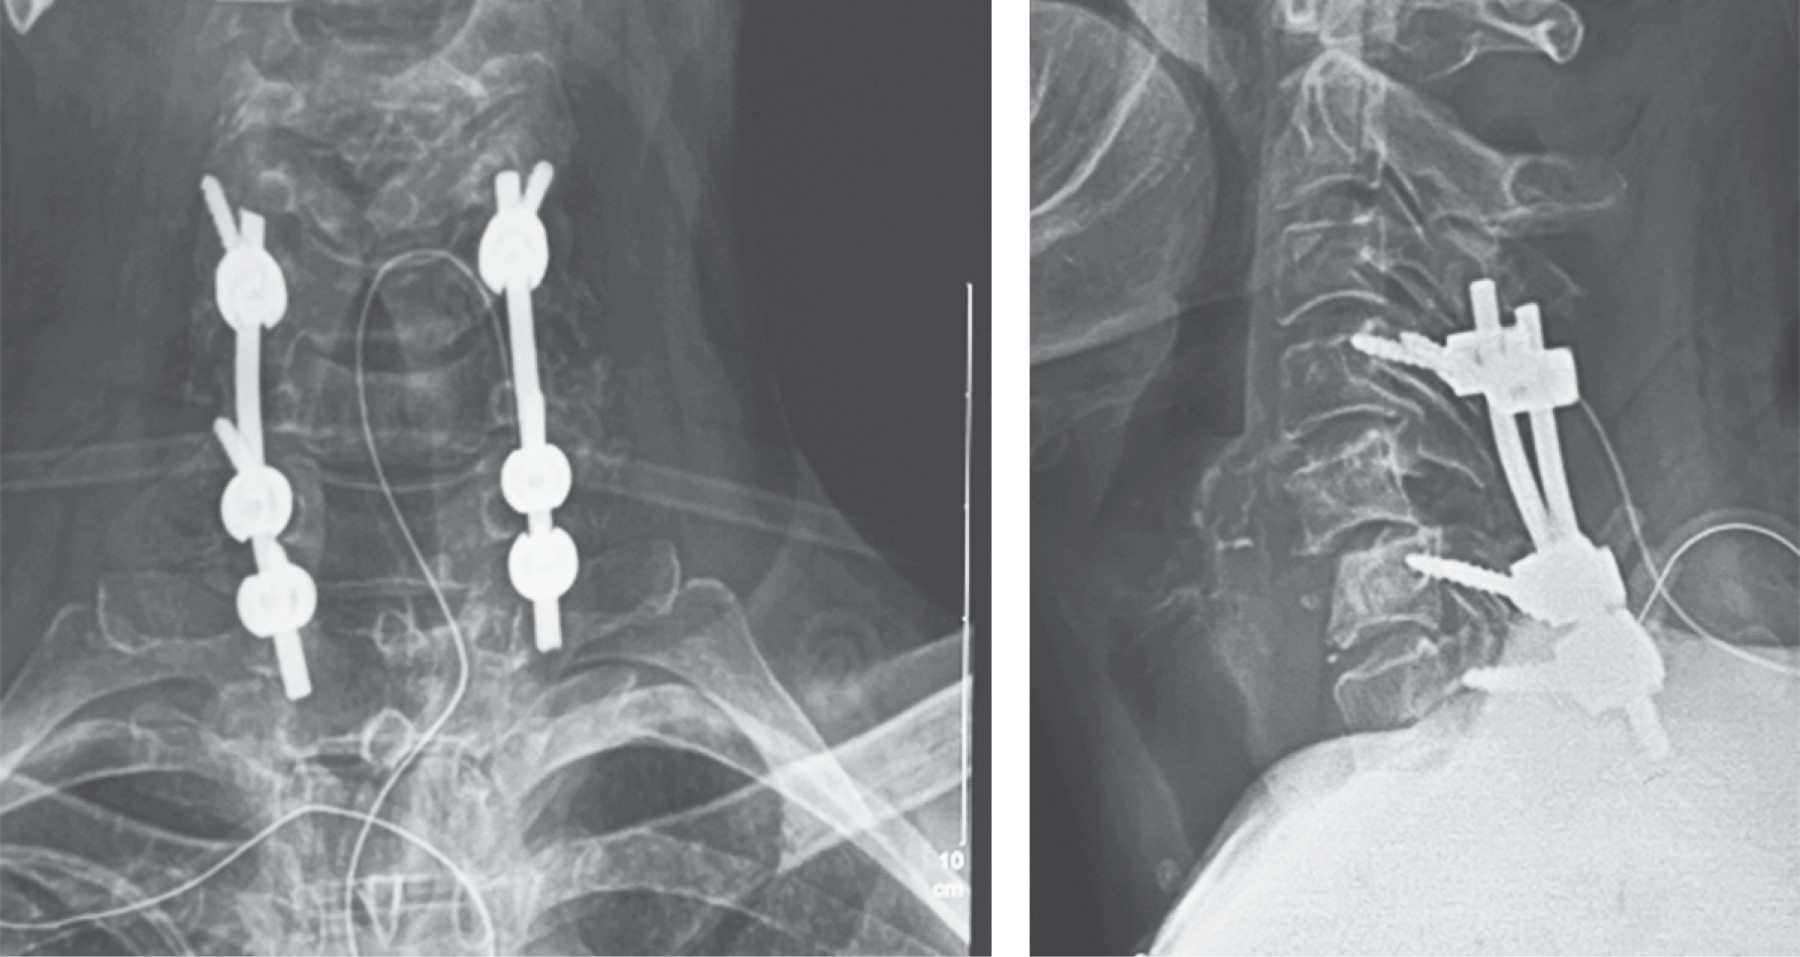

Subaxial cervical spine luxation is a frequent entity in polytraumatized patients, regularly accompanied by neurological injuries such as paraplegia or quadriplegia, requiring urgent surgical treatment in order to stabilize, align and decompress the nerve structures, sometimes it is not possible to perform this type of procedure early due to the general conditions of the patient or the conditions of the hospital units, leading to a late treatment, however, undiagnosed luxation occur, or in the worst case scenario, an inadequately treated injury with poor results that lead to an unsatisfactory evolution of the patient, with chronic pain and neurological deficit. We analyze the case of a patient with subaxial cervical spine luxation, with torpid evolution, requiring a new intervention two years after her injury, performed in three specific sequential times, achieving the patient's recovery and motor functionality.REFERENCES